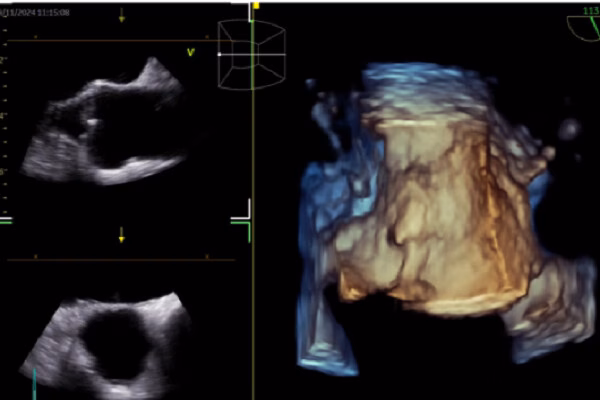

Theo bác sĩ Nhật, AI đã được ứng dụng trong nhiều lĩnh vực của tim mạch học, bao gồm điện tâm đồ (ECG), siêu âm tim, CT tim, MRI tim, đặc điểm lâm sàng, tiên lượng và quyết định lâm sàng. AI giúp dự đoán các bệnh lý như rung nhĩ, suy tim có phân suất tống máu giảm và hẹp van động mạch chủ thông qua ECG. Trong siêu âm tim, AI hỗ trợ nhận diện cấu trúc cơ tim, đo đạc tự động và hỗ trợ báo cáo và chẩn đoán.